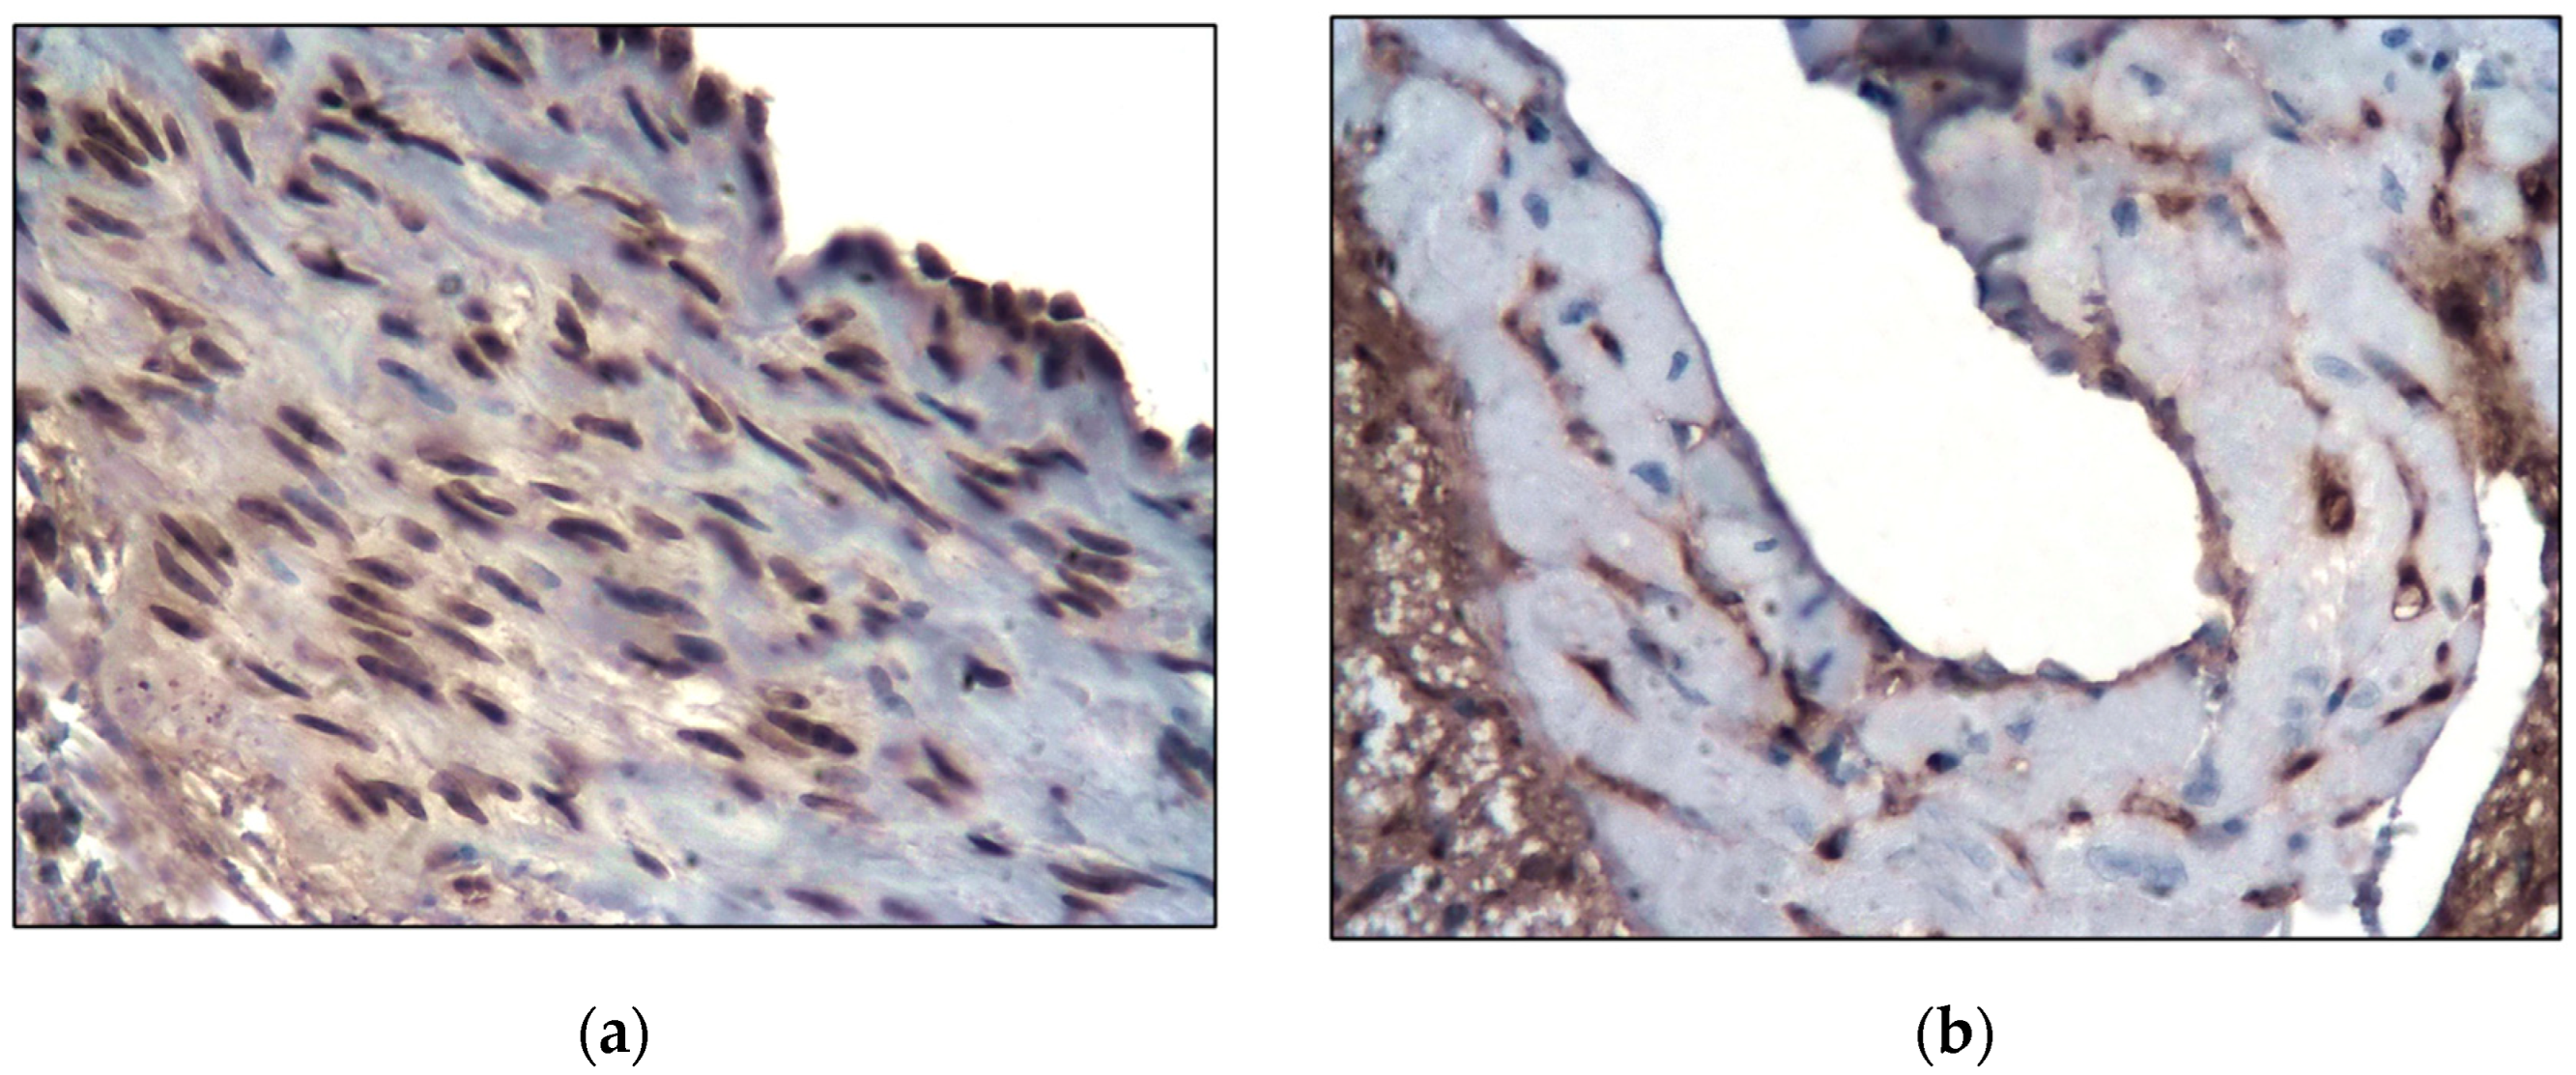

2.1. Control Group

2.2. Main Group